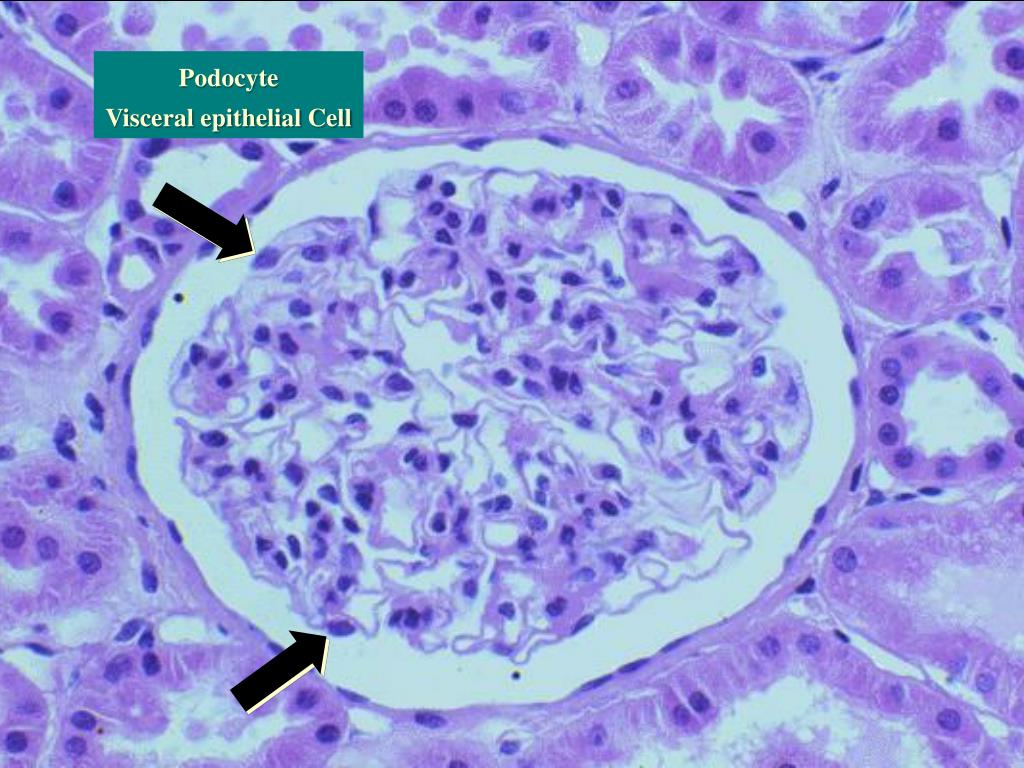

2. Podocyte Visceral epithelial Cell

Step 1 Review . Warren Kupin MD March 15, 2012. Podocyte Visceral epithelial Cell. Parietal epithelial Cell. Mesangial Cell. Endothelial Cell. Proximal Tubules. Interstitial Cells. Bowman’s Space. Normal Glomerular Capillary. Endothelial cell – fenestrated – size restriction .